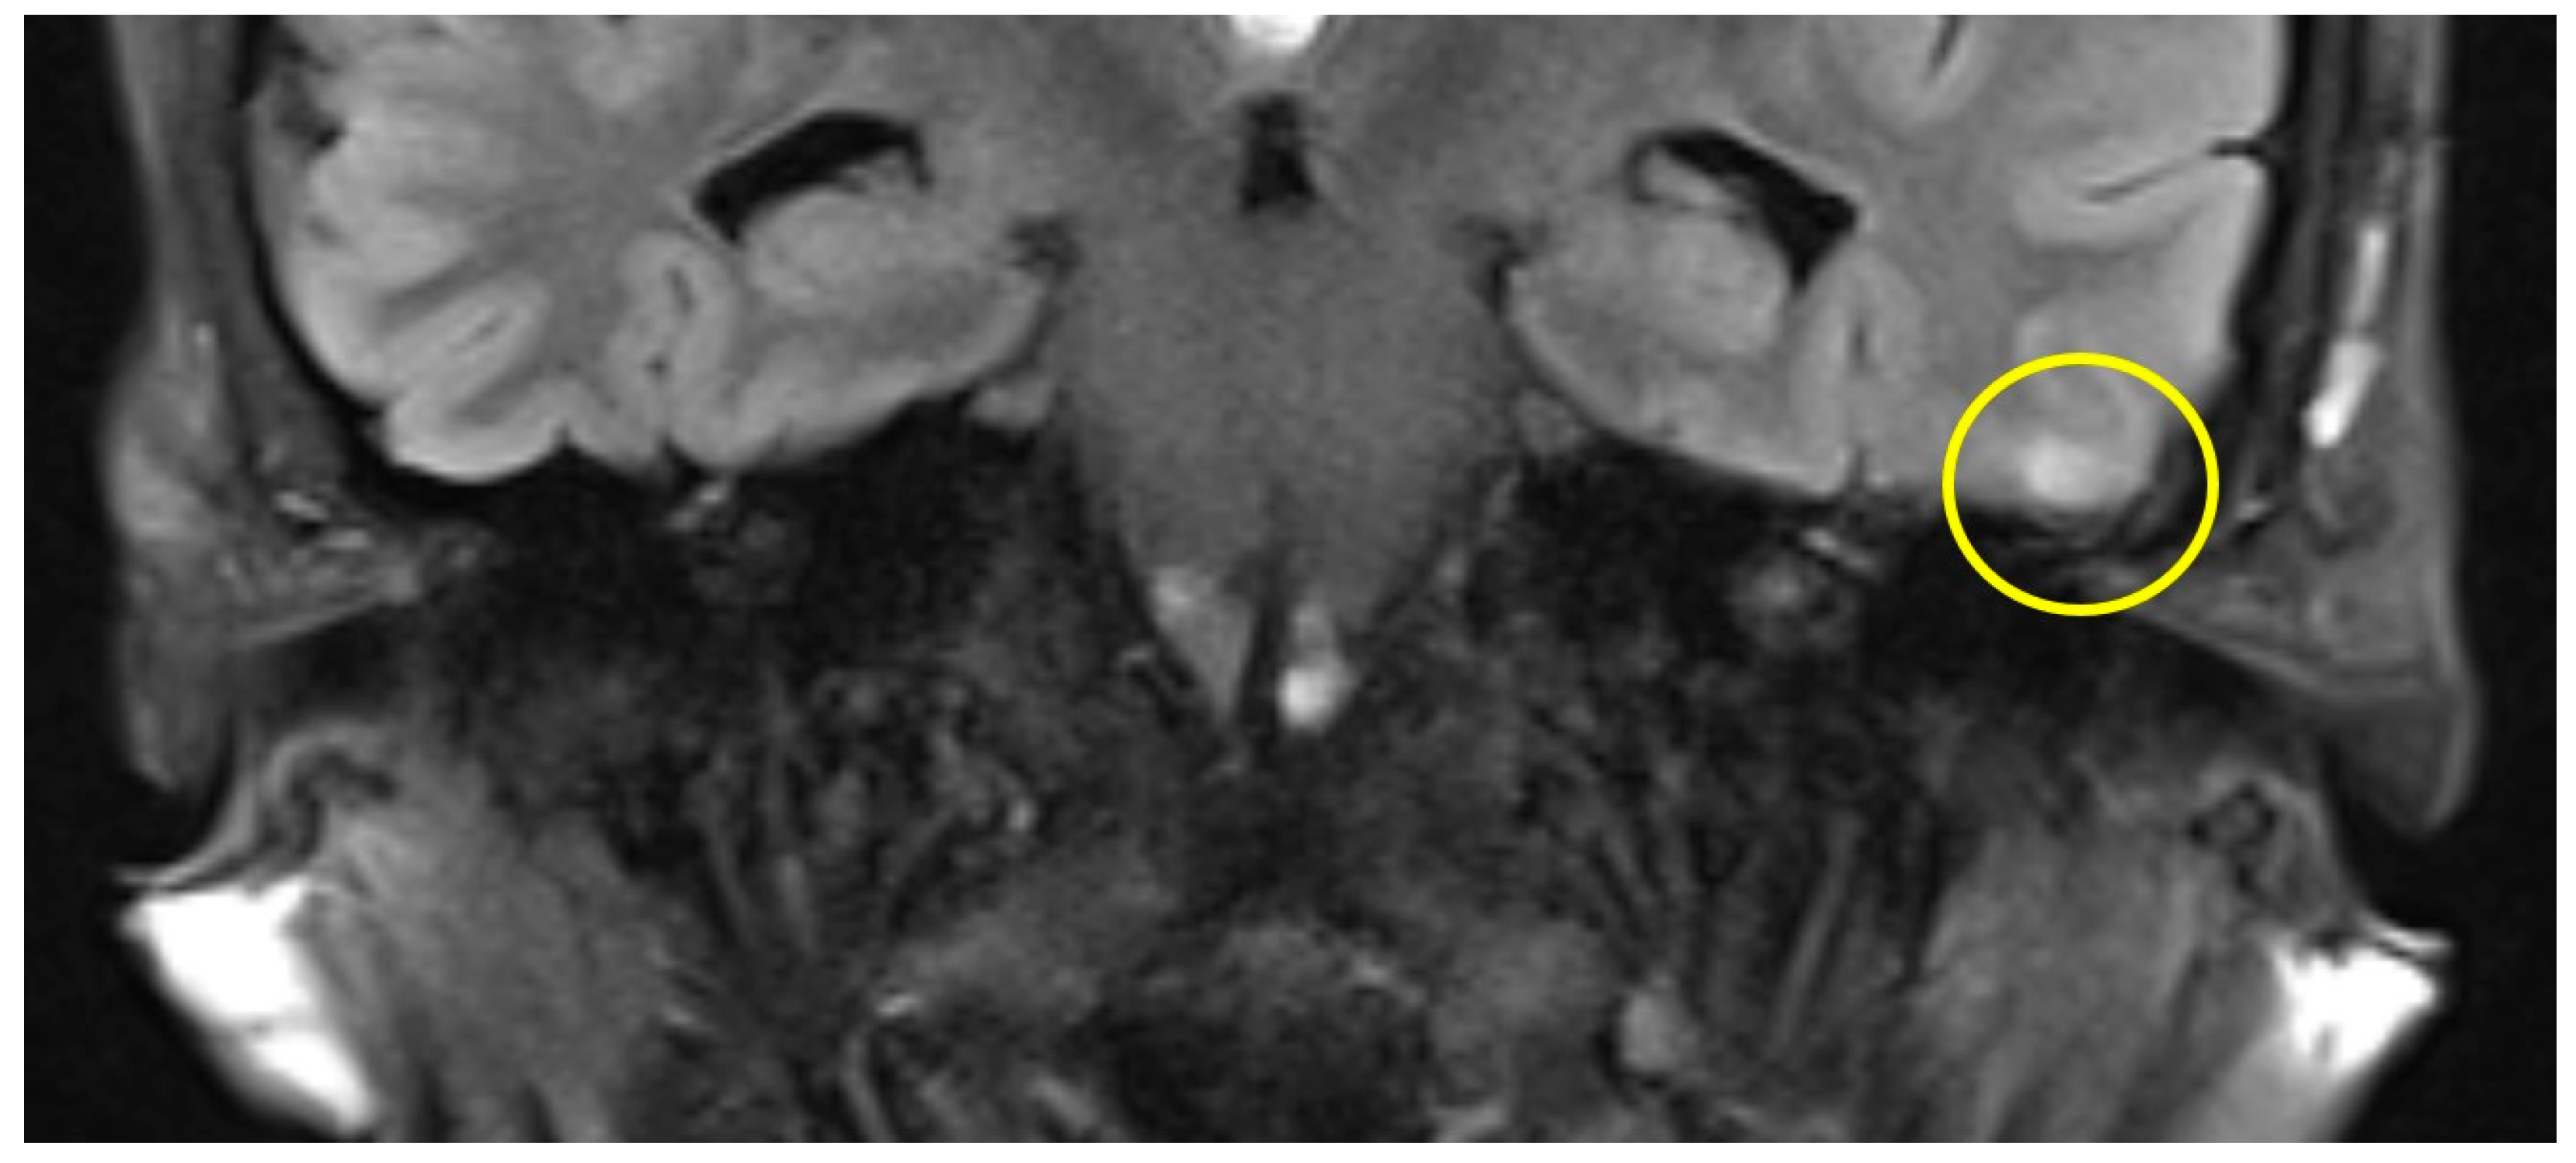

The first postoperative MR imaging of patient #3 was made 11 months after surgery and showed a very discrete focal hyperintensity on axial T2w imaging in the left temporal lobe (Figure 3). In patient #4 (Figure 4), a slight rim of gliosis was detectable on the left side in the follow-up imaging 12 months postoperatively, which can be seen in coronal T2w FLAIR (Fluid-Attenuated Inversion Recovery) imaging.

Figure 4.

Coronal T2 flair MRI of patient #4 (yellow circle = gliosis). Supplementary MR imaging can be downloaded.